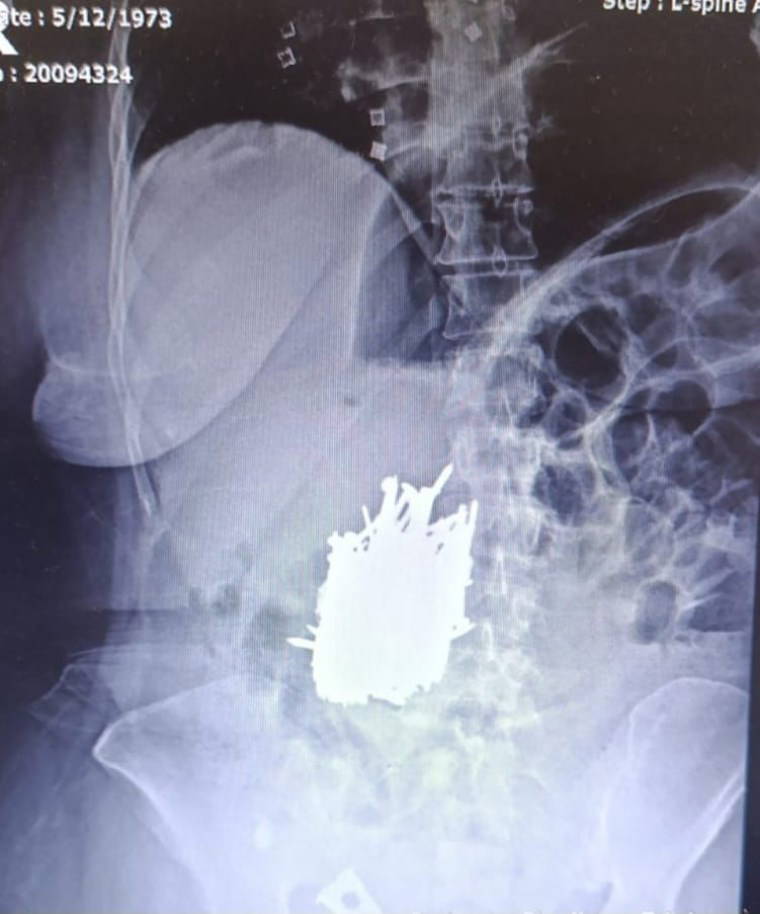

İlçede yaşayan zihinsel engelli A.K., karın ağrısı şikayetiyle Erdemli Devlet Hastanesi'ne başvurdu. Hastaya yapılan tetkik sonucunda kadının midesinde çok sayıda metal cisim olduğu tespit edildi.

Hasta, genel cerrahi uzmanı Dr. Can Terzier ve ekibi tarafından acilen ameliyata alındı ve midesinden yaklaşık 1 kilo ağırlığında çivi, inşaat demiri, kolye, toka gibi çok sayıda metal cisim çıkarıldı.